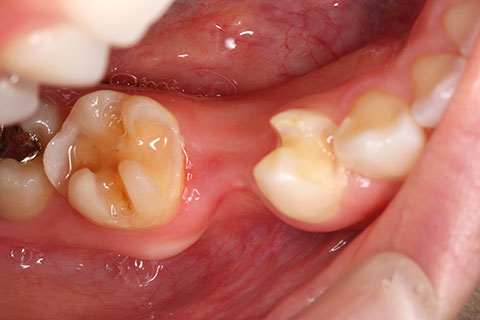

• オールセラミックの症例1

治療前

治療後

上顎前歯のデコボコと色調を改善。

年齢・性別

40歳女性

治療期間

1ヶ月

抜歯

なし

治療費

35.2万円

備考

前歯4本の変色歯及び歯列不正によるセラミック治療

治療内容

歯質を削除し、セラミック冠をセメント合着

施術の副作用(リスク)

知覚過敏、歯髄炎、荷重負担